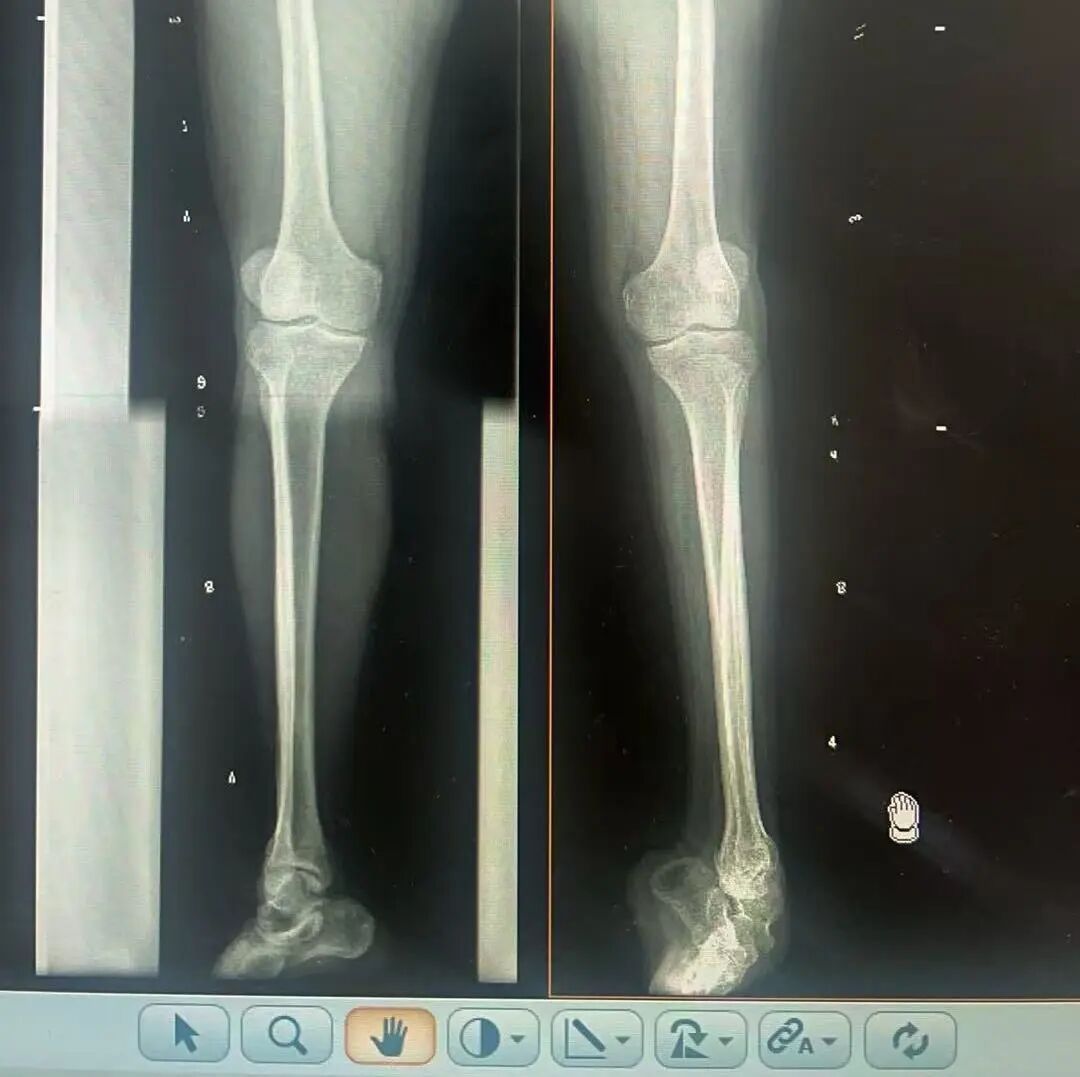

術(shù)前X光片 VS 術(shù)后治療效果

三十八年前,一紙“脊髓灰質(zhì)炎”的診斷,讓陽先生的人生染上了陰霾。闖過了急性期的鬼門關(guān),但后遺癥——嚴(yán)重的左踝馬蹄內(nèi)翻足畸形,是一道無形的枷鎖,禁錮著他的成長與自由。骨盆傾斜、雙腿不等長、左腳嚴(yán)重內(nèi)翻,他成長成人中行走的每一步,都伴隨著難以言說的艱辛。

骨科隨即為陽先生進(jìn)行了全面的檢查。診斷明確而復(fù)雜:陽先生患有脊髓灰質(zhì)炎后遺癥、左踝馬蹄內(nèi)翻足、骨盆傾斜……面對(duì)這張沉甸甸的診斷書,由肢體功能重建顯微修復(fù)學(xué)科組長鄭群龍所帶領(lǐng)的醫(yī)療團(tuán)隊(duì)沒有畏懼,“這是一個(gè)家庭38年的堅(jiān)守與期盼,我們必須全力以赴”

針對(duì)陽先生的復(fù)雜情況,鄭群龍醫(yī)師團(tuán)隊(duì)制定了詳盡的手術(shù)方案:左踝關(guān)節(jié)融合+馬蹄足畸形矯正+跟腱延長+外固定架固定術(shù)。手術(shù)的核心,正是伊里扎洛夫技術(shù)。這項(xiàng)技術(shù)如同精密的“時(shí)空建筑學(xué)”,通過微創(chuàng)安裝環(huán)形外固定架,前足-后足安裝鋼環(huán),再將足的鋼環(huán)與脛骨的固定鋼環(huán)在踝關(guān)節(jié)前、后、左、右用帶關(guān)節(jié)的螺紋桿連接,由此構(gòu)建成一個(gè)能體外牽拉調(diào)控的三維立體構(gòu)型,在術(shù)后進(jìn)行精準(zhǔn)、緩慢的調(diào)整,一寸一寸逐步將畸形的骨骼、軟組織恢復(fù)到正常位置。